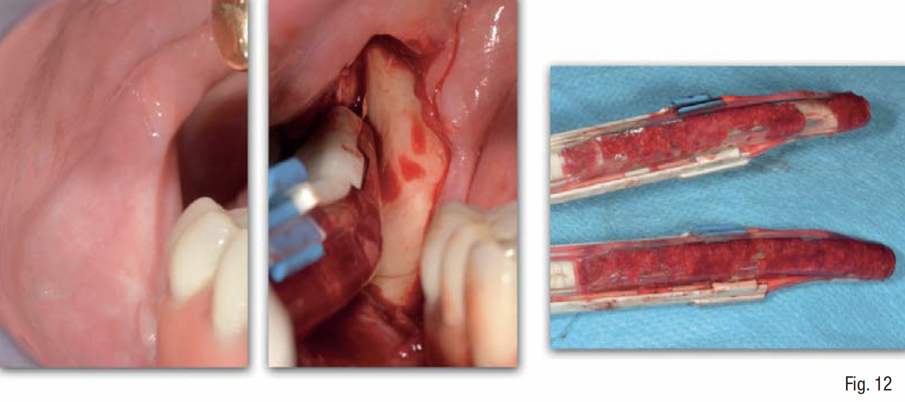

La corticale esterna del sito ricevente è stata perforata (Fig. 11) al fine di promuovere la migrazione delle cellule osteogeniche e osteoprogenitrici e la rivascolarizzazione dell’innesto osseo al di sotto della griglia. L’osso autologo del paziente è stato mescolato in rapporto 1:1 ad osso eterologo di origine bovina ad alta porosità (Zcore®, Osteogenics Biomedical, Lubbock, Texas), tutto idratato con sangue venoso periferico del paziente (Fig. 12). La griglia customizzata è stata quindi riempita con il materiale da innesto, posizionata a livello della superficie vestibolare del mascellare, e fissata con 5 mini-viti di sintesi in titanio di lunghezza 6-9 mm (BTK screw, Biotec Srl, Dueville, Vicenza, Italy), verificandone la perfetta stabilità e la conseguente assenza di micro- o macro- movimenti. Al fine di rispettare il principio di “esclusione cellulare” della GBR, al di sopra della griglia è stata applicata una membrana in collagene cross-linkato (Cytoplast RTM, Osteogenics Biomedical, Lubbock, Texas), fissata tramite chiodini di titanio sul lato vestibolare e suturata alla mucosa sul lato palatale (Figg. 13-17).